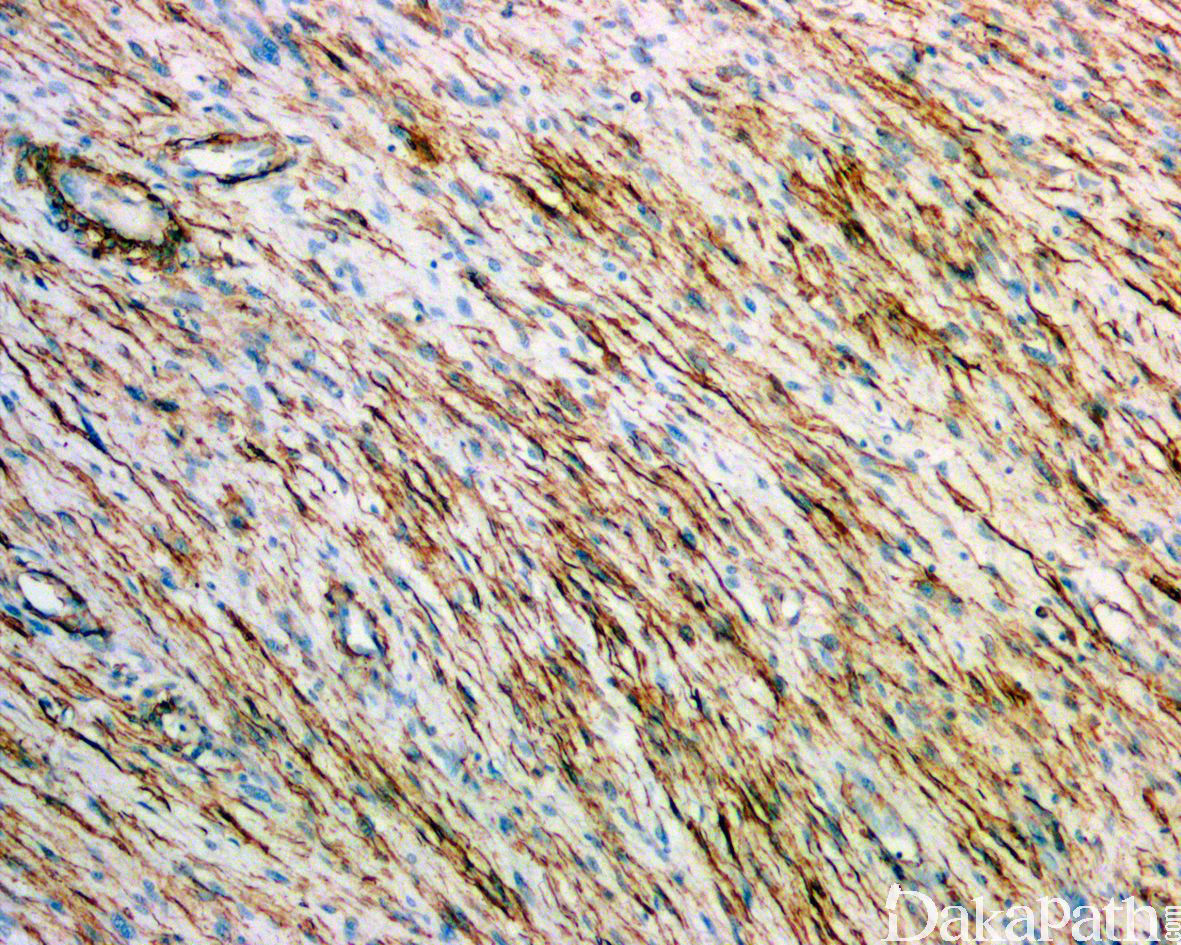

免疫组织化学染色,绝大多数的 DDLPS 弥漫强表达 p16 蛋白(核和质表达),是诊断 DDLPS 最敏感的标志物,但缺乏特异性,许多与之形态学相似的肿瘤,特别是高级别肿瘤(如平滑肌肉瘤和肉瘤样癌等)亦可弥漫表达 p16。由于 DDLPS 一致性的存在 12q14-15 区域的扩增和过表达,而 MDM2 蛋白和 CDK4 蛋白的强表达与相应的基因扩增存在高度的一致性,因此免疫组织化学染色 MDM2 和 CDK4 的共表达(均为弥漫核表达)对于诊断 DDLPS 具有较大的帮助。在与 ALT/WDLPS 之外的其他类型的脂肪源性肿瘤的鉴别诊断中,联合应用 p16. MDM2 和 CDK4 对于诊断 DDLPS 具有高度的敏感性和特异性,93%的 DDLPS 表达上述 3 个标志物中的至少 2 个,72%表达全部 3 个标志物。但在 DDLPS 与非脂肪源性的肿瘤鉴别诊断时,上述 3 个标志物的特异性则明显不够;此时,应用荧光原位杂交(FISH)检测 MDM2 基因的扩增对于诊断 DDLPS(在适当的组织学背景下)具有高度的特异性和敏感性,尤其是在小活检标本、未见典型的 ALT/WDLPS 成分、低级别去分化和少见特殊类型的 DDLPS 诊断时更是如此。MDM2 基因的扩增目前普遍认为是诊断 ALT/WDLPS 和 DDLPS 的金标准,需要指出的是,MDM2 基因扩增并非 ALT/WDLPS 和 DDLPS 所特有,其他常见存在 MDM2 基因扩增的肿瘤还包括低级别中央型骨肉瘤、骨旁骨肉瘤以及原发的心脏内膜肉瘤等。约半数左右的 DDLPS 可局灶或弥漫表达 CD34,去分化成分一般不表达 S100 蛋白,伴有肌纤维母细胞分化者可表达 SMA 和 MSA 或结蛋白[23],伴有横纹肌和平滑肌分化者可分别表达 MyoD1 和 H-caldesmon,具有脑膜上皮瘤样漩涡特征的 DDLPS 可表达 SMA 和 Claudin-1 提示其肌纤维母细胞或神经束膜分化的特征。新近发现,约 6%的 DDLPS 可见 H3k27me3 的表达缺失易与恶性外周神经鞘膜瘤(MPNST)混淆,约 11%的 DDLPS 可见 STAT6 基因扩增从而局灶或弥漫表达 STAT6 易误诊为孤立性纤维性肿瘤(SFT)。